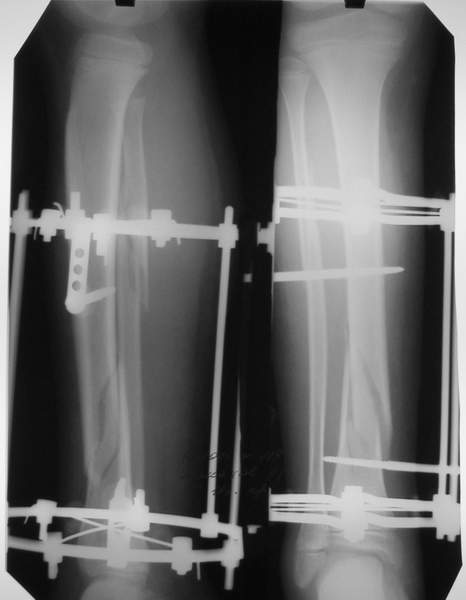

В аттачтах №№ 1 и 2 - примеры, когда 2 кольца не позволили послеоперационно

исправить смещение фрагментов большеберцовой (по ширине и вальгусное).

А казалось бы (#2) - поиграй на штангах и все влетит.

Оперировал не я

:-)

2